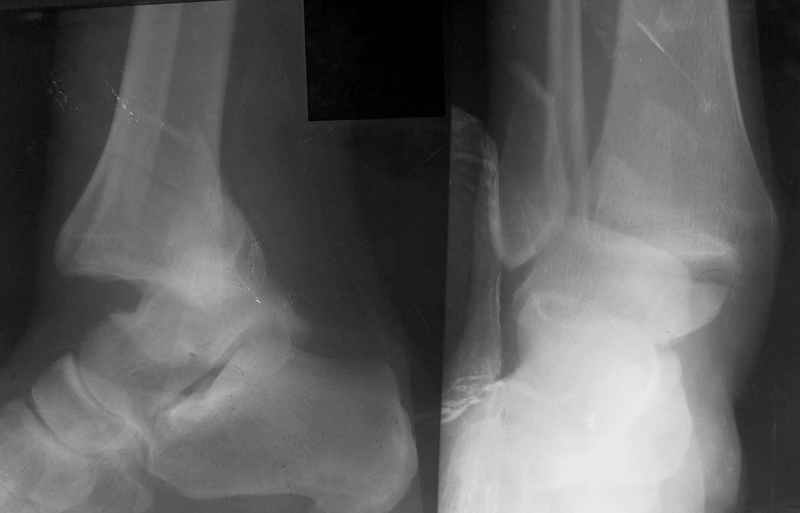

Re: Открытый переломо-вывих стопы.

Стабильность г\ст сустава обеспечивается во-первых наружной лодыжкой (ключ), во-вторых задним краем б\б кости, в-третьих связками синдесмоза и межкостной мемраной, только в-четвертых медиальной лодыжкой (дельтовидной связкой. Это классика! А пяточной кости и плюсневых костей здесь нет! зачем их фиксировать? см. вложенный файл.